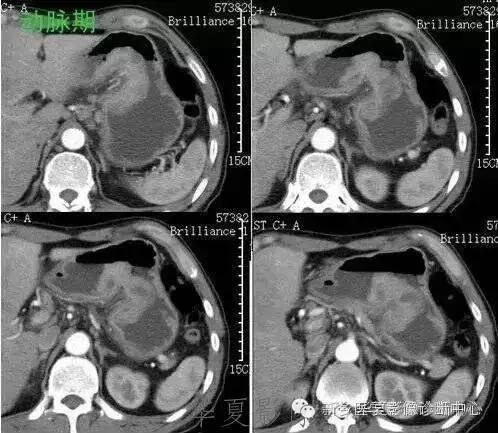

肝脏黑色素瘤

原发于肝脏的恶性黑色素瘤极其罕见。肝脏原发恶性黑色素瘤临床表现及体征均无特征性,与其他肝脏占位性、 肿瘤性病变无法区分,此为该病的临床特征。

肝脏恶性黑色素瘤的超声和 CT多表现为肝脏增大,肝内单发、 多发占位病变或弥漫性、 结节性改变, 占位性病变可为实性、 囊性、 囊实性改变,但上述改变无明显特异性, 与其他肝脏恶性肿瘤无法区分。MR T1 加权呈高信号、 T2 加权呈低信号